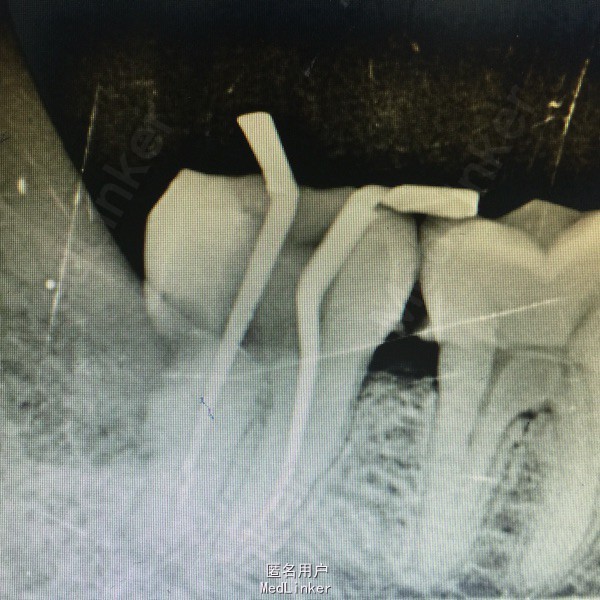

患者男性,40岁,右下后牙肿胀不适数日,近日疼痛加重张口受限,来院就诊。

查体:右面部肿胀,开口型正常,张口受限,48盲袋附着,溢脓,X线示48近中水平阻生,47远中邻面龋坏,龋坏深达牙髓腔。

诊断:48阻生齿,47牙髓炎 处理:48抗炎治疗,炎症控制后拔除48,数日后局麻下,47开髓揭髓顶,拔髓,冲洗进行根管疏通及测量,EDTA机用镍钛器械根管预备,次氯酸钠冲洗,进行热牙胶充填,Zoe暂封观察,建议嵌体修复。